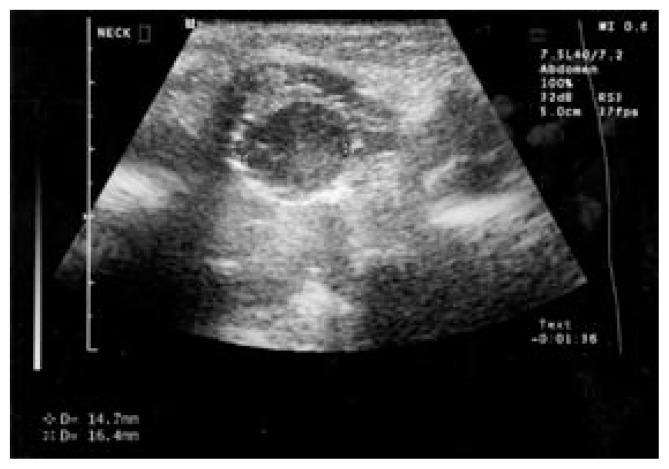

A newborn female with a smooth mass in the region of the base of the tongue.